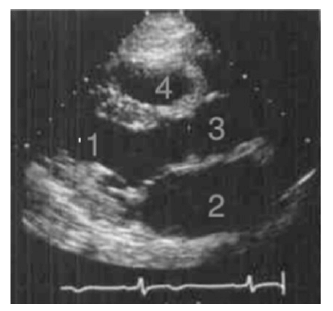

Um paciente comparece ao consultório do cardiologista para exames de rotina. Segundo o médico, nos exames não se observou qualquer alteração, mas o paciente foi ao ambulatório de clínica médica, pois desejava saber o significado do número 1 no exame de imagem ecocardiográfica que foi realizado. Considerando que a imagem apresentada é obtida na incidência longitudinal paraesternal durante a sístole, nesse caso clínico, o médico informou corretamente ao paciente que, na imagem, o número 1 corresponde ao (à)